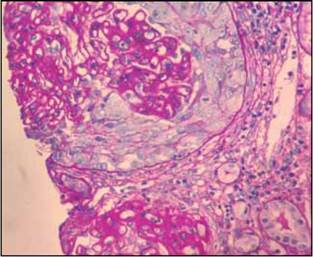

Se confirmó el diagnóstico de síndrome nefrótico y se decidió solicitar biopsia renal que reportó hallazgos de nefropatía membranosa con un componente agudo necrosante de proliferación extracapilar (Figuras 1-3).

Por otro lado, la evidencia histopatológica de proliferación de células epiteliales viscerales o parietales en el espacio de Bowman se conoce como proliferación extracapilar. Cuando el daño glomerular es muy severo, se asocia con ruptura de la pared capilar o de la cápsula de Bowman lo que permite el ingreso de proteínas plasmáticas y material inflamatorio al espacio de Bowman, configurando una forma de crescencia o medialuna, hallazgo que generalmente implica un deterioro acelerado de la función renal en el contexto clínico de una glomerulonefritis rápidamente progresiva, generalmente asociada a vasculitis, enfermedad de Goodpasture o a otras glomerulonefritis agudas y severas de cualquier otra etiología 5.